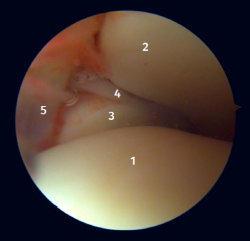

El 20% del LTPA es intraarticular(7). Cuando realizamos un acceso anteromedial del tobillo dirigiendo el artroscopio hacia lateral podemos ver las fibras distales del LTPA con su disposición oblicua y su continuación con el ligamento peroneo-astragalino anterior (Figura 2). Si avanzamos dentro de la articulación tibioastragalina, veremos la articulación tibioperonea distal con el receso sindesmal ocupado de tejido sinovial (Figura 3).

Figura 2. Visión artroscópica anterolateral del tobillo derecho. 1: cúpula astragalina; 2: cara anterior de la tibia; 3: peroné; 4: fibras distales del ligamento tibioperoneo anterior; 5: ligamento peroneo-astragalino anterior.

Figura 3. Visión artroscópica anterolateral de un tobillo derecho al introducirnos en la tibioastragalina. 1: cúpula astragalina; 2: cara articular de la tibia; 3: peroné; 4: articulación tibioperonea distal; 5: fibras distales del ligamento tibioperoneo anterior.